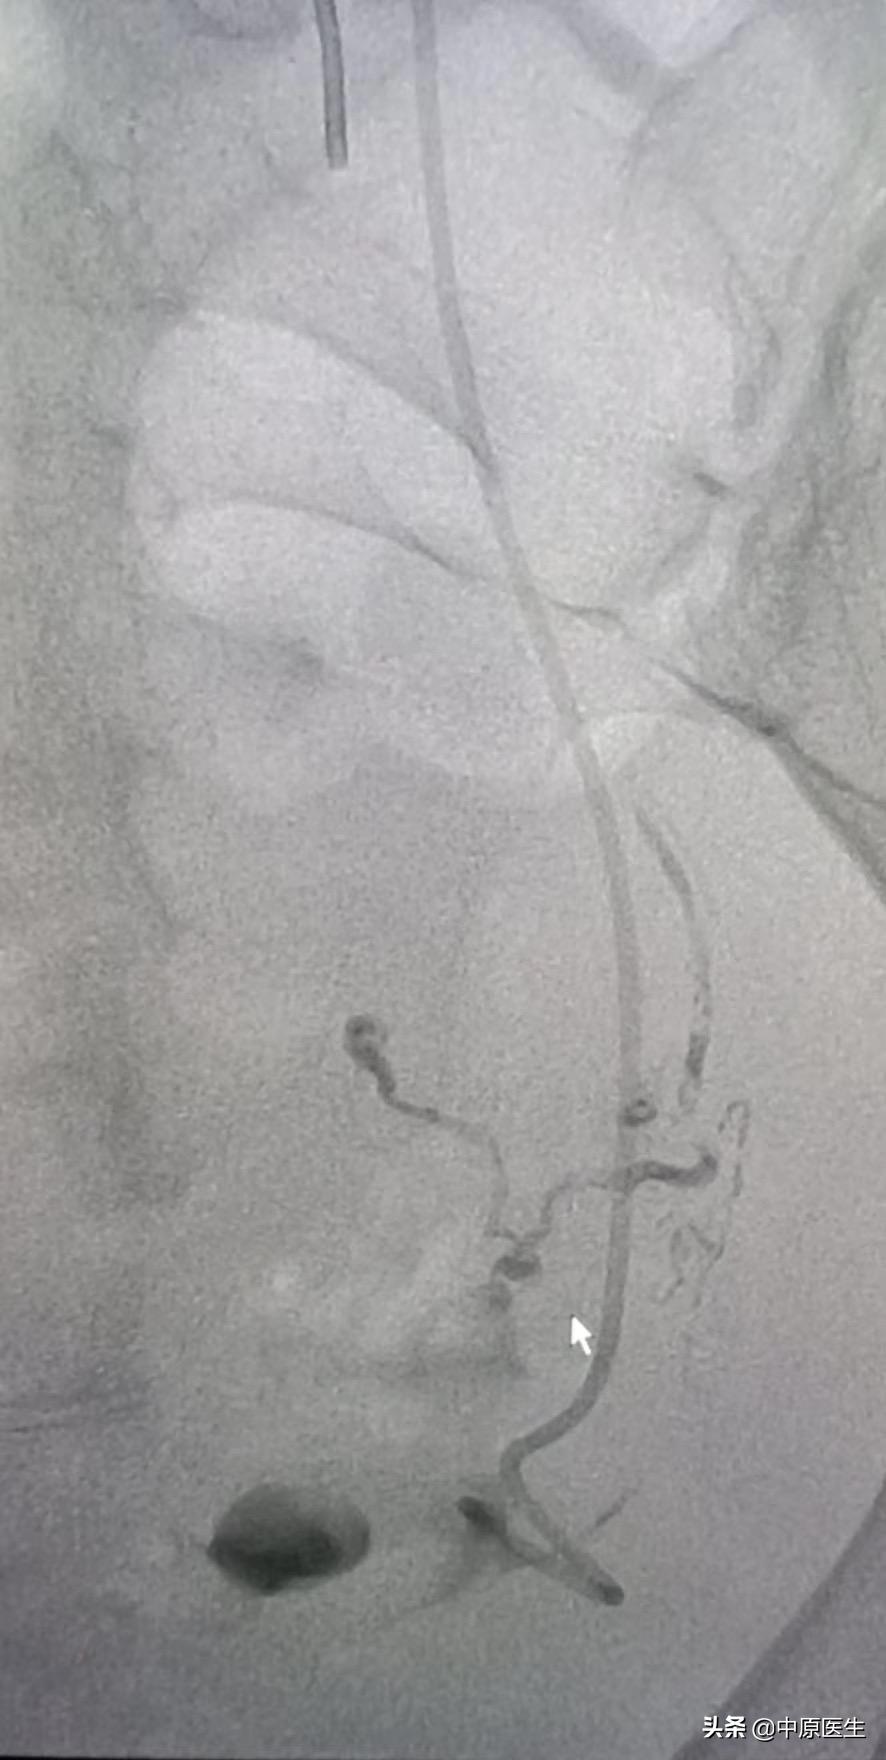

我处理好门诊事宜,十点赶往导管室,按标准预防做好术前防护、术前准备工作。在导管室的护士、技师等积极配合下,手术顺利开展,造影显示左侧子宫动脉近宫颈处有一破口、形成假性动脉瘤,假性动脉瘤破溃,造影剂快速流入宫腔内(相当于找到了河流的决口处);紧急用生物胶栓塞该破口及其远、近端血管(相当于堵住了决口及其上下游,上游流不进来、下游的倒灌不了),复查造影未见造影剂外渗、动脉瘤、静脉早显等异常血管影(成功止血)。然后选择双侧髂内动脉各分支造影未见明显异常血管,再予右侧子宫动脉栓塞。半小时顺利完成手术,病人生命体征平稳。安全送回病房,继续药物治疗。